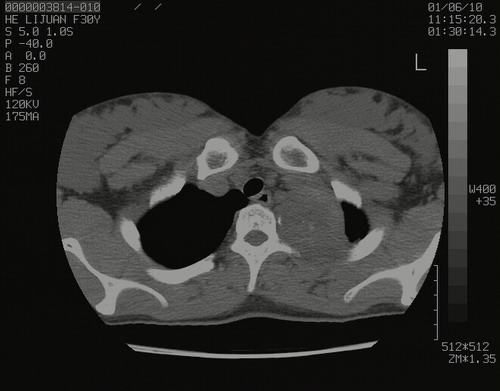

怀孕3个月时(2009-3至4月间),自述突感左侧前后胸疼痛1天,以前胸明显,随后偶感闷痛,余未见异

左肺尖脊柱旁沟肿块,境界清楚,边缘光滑,密度不均,内有多发点片状钙化,考虑良性肿瘤,骨软骨瘤或神经源性肿瘤可能,肺错构瘤不除外。

考虑:神经源性病变,神经鞘瘤可能性大;

鉴别:纵膈胸膜孤立性纤维瘤、castleman's、畸胎瘤、血管瘤、滑膜肉瘤。

左后上纵隔见一类圆形肿块影,外侧边界清,密度不均匀,内可见点状钙化影,增强呈不均匀强化,考虑神经源性肿瘤可能。期待病理结果。